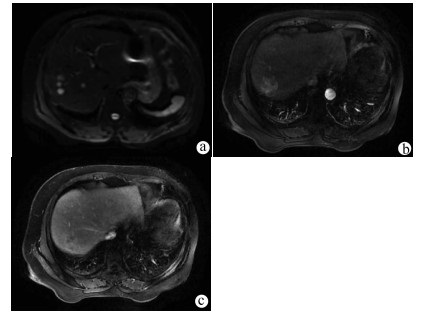

A case of primary hepatic neuroendocrine tumor

LING JK, WANG M, YUAN J, et al. CT and MRI findings of primary hepatic neuroendocrine neoplasm[J]. Chin J Oncol, 2017, 39(8): 600-606. DOI: 10.3760/cma.j.issn.0253-3766.2017.08.008.

李家开, 王敏, 袁静, 等. 肝脏原发性神经内分泌肿瘤的CT和磁共振成像表现[J]. 中华肿瘤杂志, 2017, 39(8): 600-606. DOI: 10.3760/cma.j.issn.0253-3766.2017.08.008.

AO WQ, WU D, ZENG MS, et al. CT and MRI diagnosis of primary hepatic neuroendocrine carcinoma[J]. Radiol Pract, 2013, 28(10): 1032-1036. https://www.cnki.com.cn/Article/CJFDTOTAL-FSXS201310015.htm

敖炜群, 吴东, 曾蒙苏, 等. 原发性肝脏神经内分泌癌的CT和MRI诊断[J]. 放射学实践, 2013, 28(10): 1032-1036. https://www.cnki.com.cn/Article/CJFDTOTAL-FSXS201310015.htm